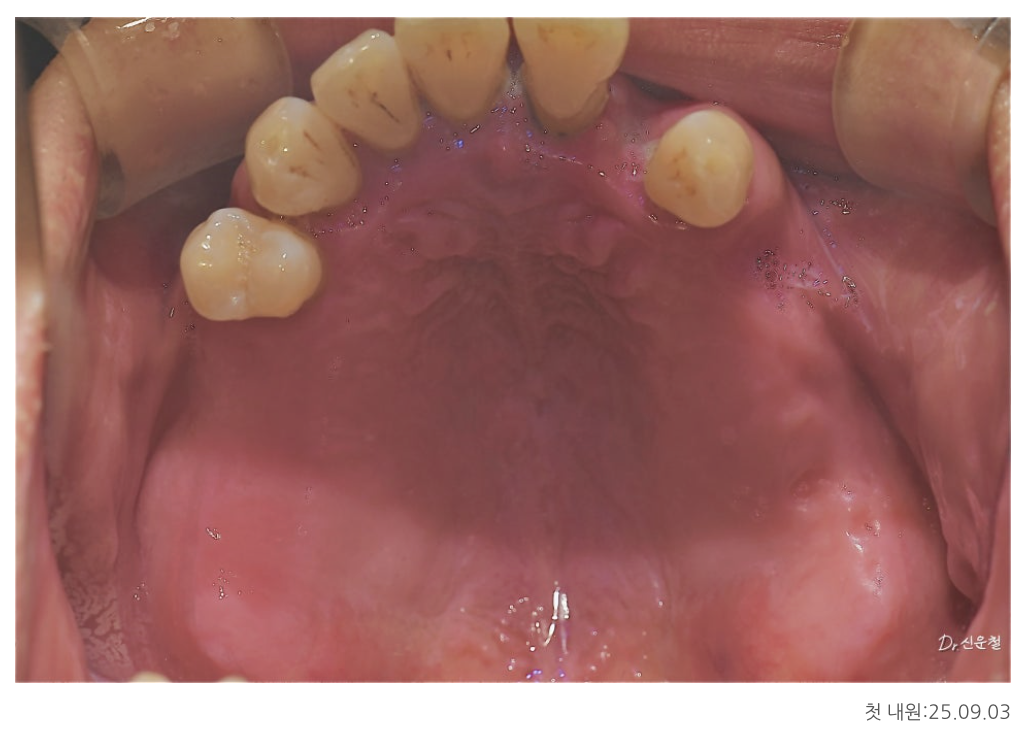

위턱·아래턱 상태 정밀 진단

위턱

남아 있는 치아 중 좌측 견치 1개만 보존 가능

견치는 뿌리가 길어 치조골 지지력이 비교적 좋은 치아

그 외 치아는 염증이 심하고 치조골 지지가 어려운 상태

다수의 치아 상실

앞니만 일부 남아 있는 상태

상악동 거상술을 통한 기초 치료

위턱 어금니 부위는

오래전 치아를 상실해 임플란트를 바로 심기엔 뼈 높이가 부족했습니다.